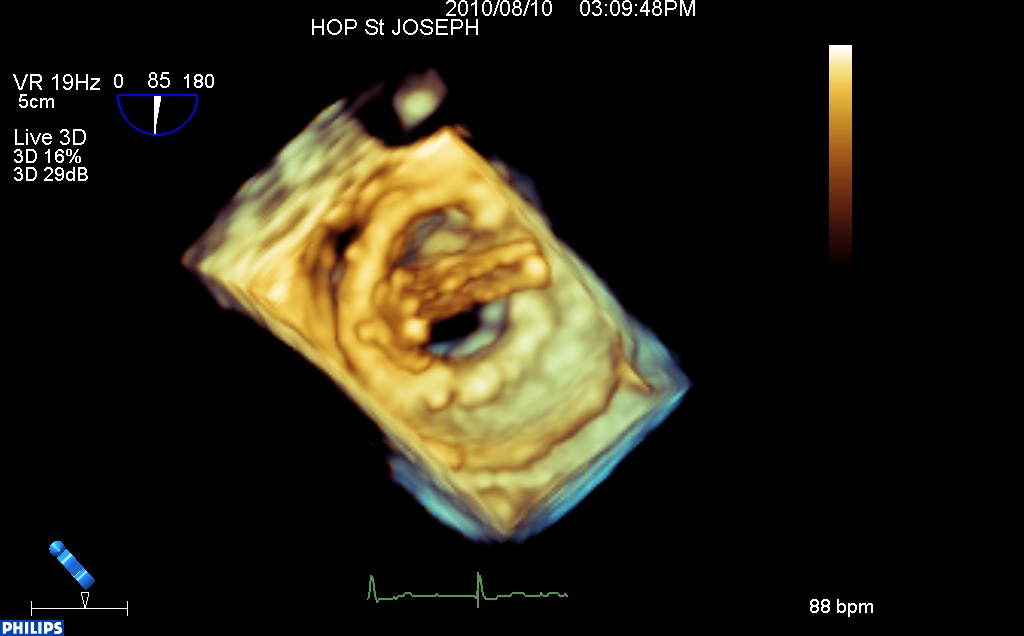

Ci-dessous, en 3d « full volume » avec Doppler couleur, les trois fuites sont bien visibles en rouge, confirmant le caractère non obstructive de cette thrombose.

Ailettes fermées :

thrombose non obstructive de prothèse mitrale 3d couleur from fish Nip echocardiographie on Vimeo.

Ailettes ouvertes :